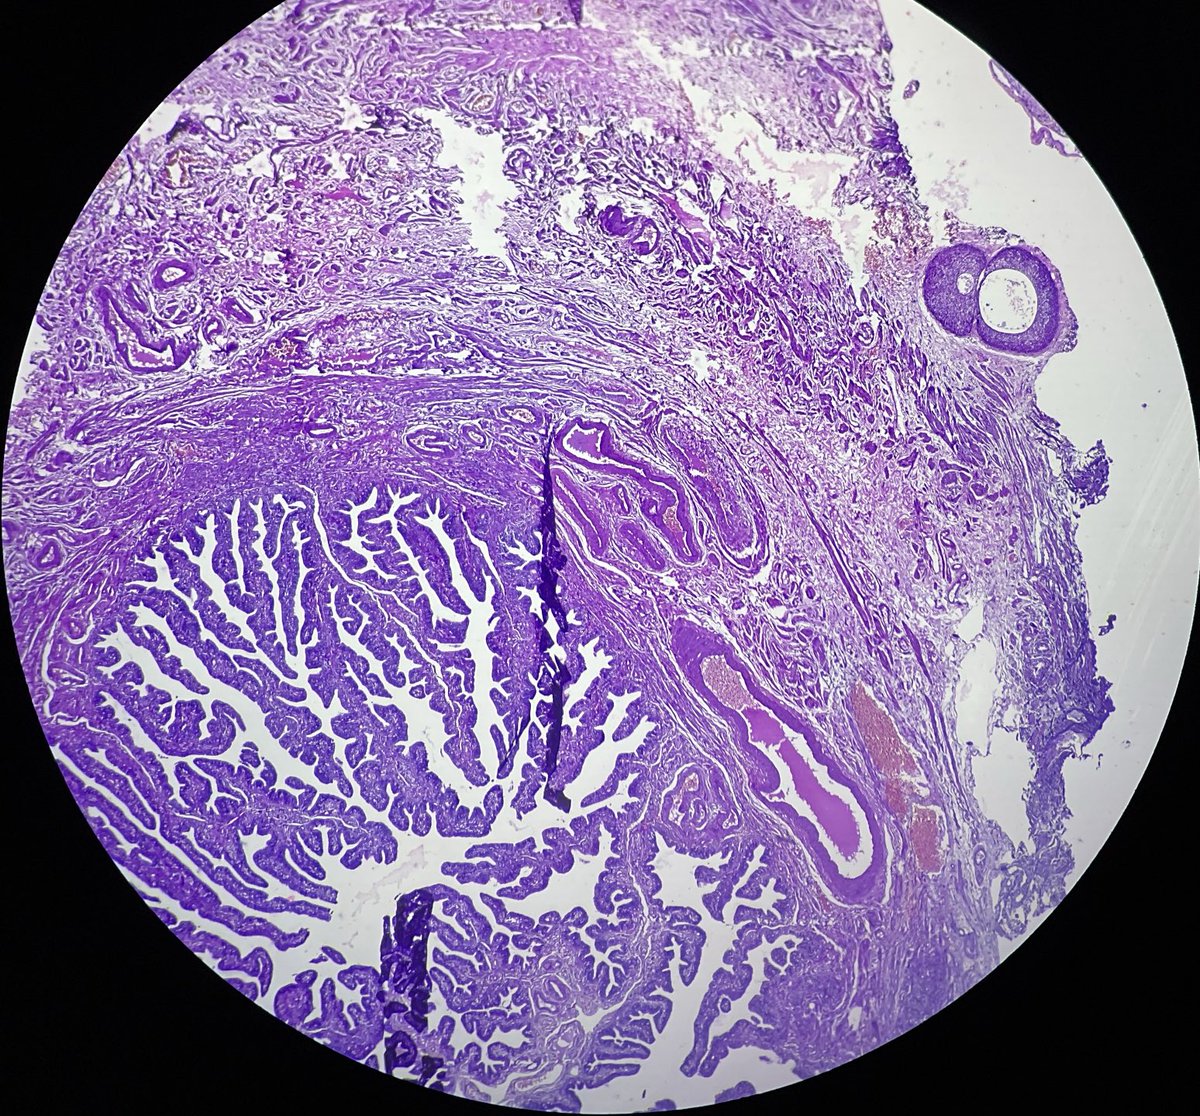

Mucinous lesions of the endometrium Papillary endometrial proliferations with mucinous metaplasia -Mucinous glands with intraglandular simple papillary structures How would you sign out this endometrial biopsy? See next post 👇 Dr. Wong #isgyp #PathTwitter #PathX #pathresidents

Papillary endometrial proliferations with mucinous metaplasia

-Mucinous glands with intraglandular simple papillary structures

How would you sign out this endometrial biopsy?